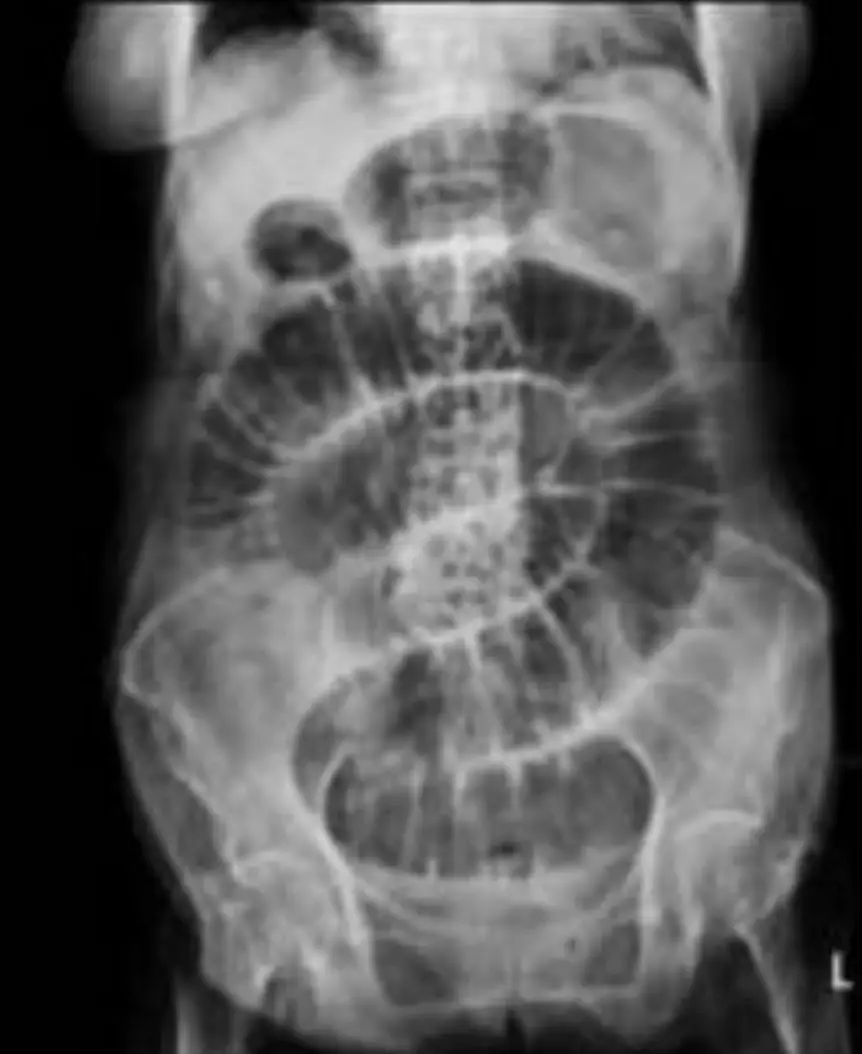

一位87歲女性,主訴昨晚排便後腹脹嘔吐,至今無排氣。觸診發現右側腹股溝有一突出物,其腹部KUB如下圖,最有可能之診斷為何? 圖片描述

• 影像:腹部 KUB 顯示多發性階梯狀擴張小腸環,結腸氣體消失,符合高位腸阻塞。